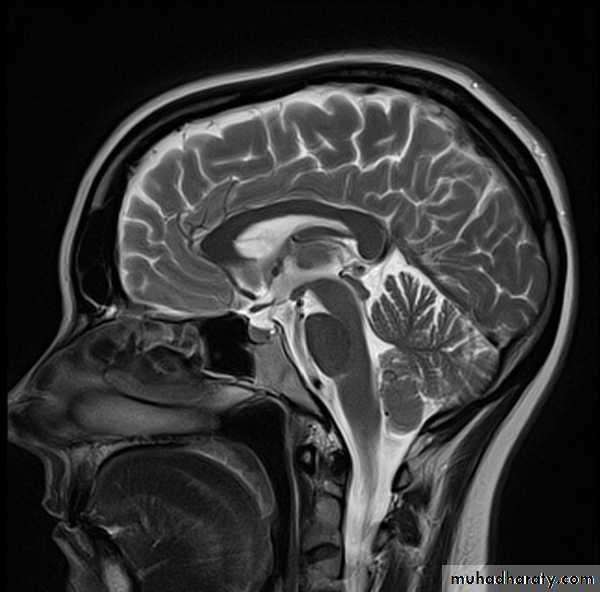

Common CT findings of traumatic brain injury